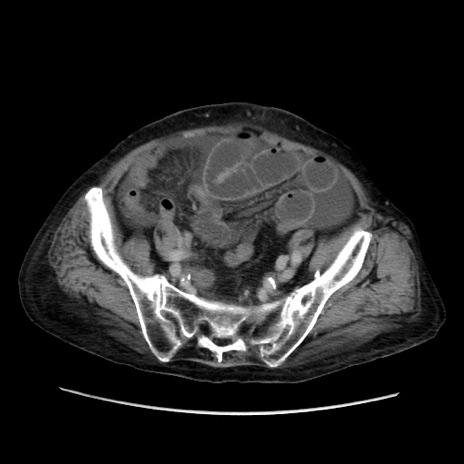

症例31(横断像)

【症例】80歳代 女性

【主訴】腹部膨満感

【現病歴】他院にて肝硬変にてフォロー中。1週間前から便秘、腹部膨満感、臍部腫瘤あり受診となる。

【既往歴】肝硬変

【身体所見】腹部膨隆あり、皮膚変化なし、疼痛なし。

【データ】WBC 4600、CRP 0.25